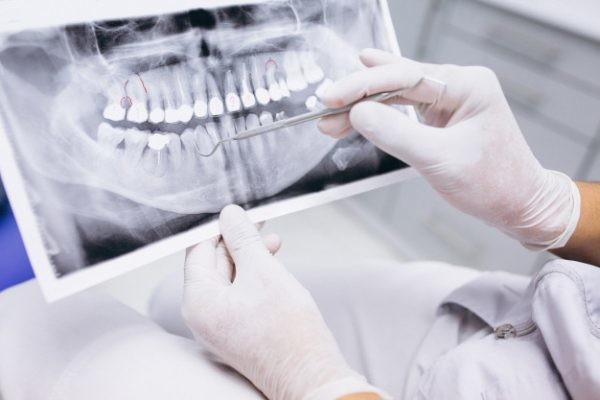

A dental professional or specialist (usually an endodontist) may diagnose a fracture during a root canal procedure if they can see a crack. If the fracture occurs after the procedure, they might need to take X-rays, which may show the fractured root characteristically shaped like the letter J, or the specialist may also use a diagnostic method known as transillumination, where they shine a light through your tooth to detect any fracture lines.